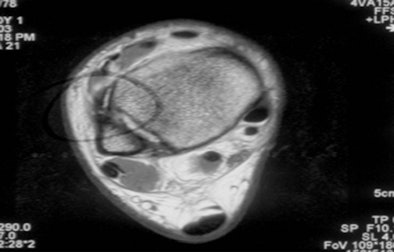

![]() |

| MR axial image of an NFL running back shows damage to the anterior tibiofibular ligament and grade III injury. The player missed the remainder of the season. |